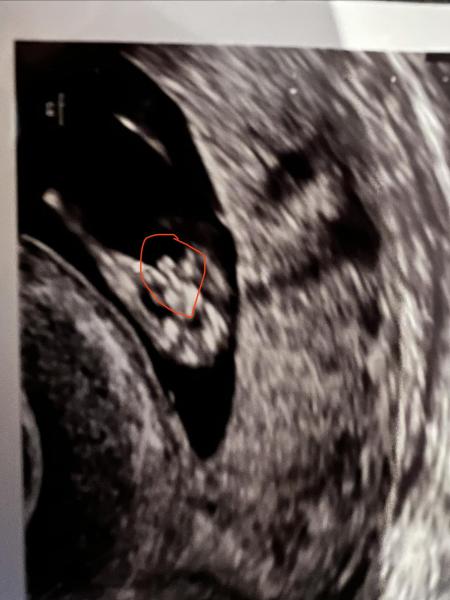

Hallo:)  Ich habe von meinem Frauenarzt ein frühes Jungen Outing bekommen in der 11+4 SSW. Ich find es noch sehr früh… allerdings ja man sieht was zwischen den Beinen… was meint ihr? das Bild ist von unten aufgenommen...also praktisch der Po

Bild zu Frühes Jungen Outing in 11+4 - Schwanger - wer noch? Rund um die Schwangerschaft

Ich finde das auch recht früh. Aber keiner von uns ist ausgebildet in Ultraschalldiagnostik, deshalb kann dir hier auch niemand sagen, was man da sieht – es kann ja auch ein Querschnitt der Nabelschnur etc. sein. Ich würde deinem Gyn jetzt erstmal vorsichtig glauben. Blaue Babykleidung würde ich allerdings noch nicht kaufen. So richtig zuverlässig ist die Bestimmung oft erst in der 16. SSW oder später. Und tatsächlich irren Ärzte sich manchmal, das sagte mir sogar mein eigener Arzt. LG

Antwort auf Beitrag von Lena0801

Hallo, so früh würde ich mich definitiv nicht darauf verlassen. Das kann genauso gut ein Mädchen sein, wo die Nabelschnur getroffen wurde. Oder aber geschwollene Schamlippen oder einfach noch der Nub der zu dieser Zeit ja doch noch sehr ähnlich aussieht. Hier heißt es also weiterhin warten und auf Bestätigung warten, dass es wirklich bei einem kleinen Jungen bleibt. 😉

Sah bei mir zu diesem Zeitpunkt genauso aus. Meine Gyn hat mir dann auch gesagt, dass es ein Junge ist, was auch später bestätigt wurde. Ich denke, du kannst darauf vertrauen, deine Ärztin hat genug Erfahrung und wenn sie nicht sicher gewesen wäre, hätte sie dir das auch mitgeteilt

Meinst du auf dem Bild sind auch die Hoden zu erkennen ? 🙊